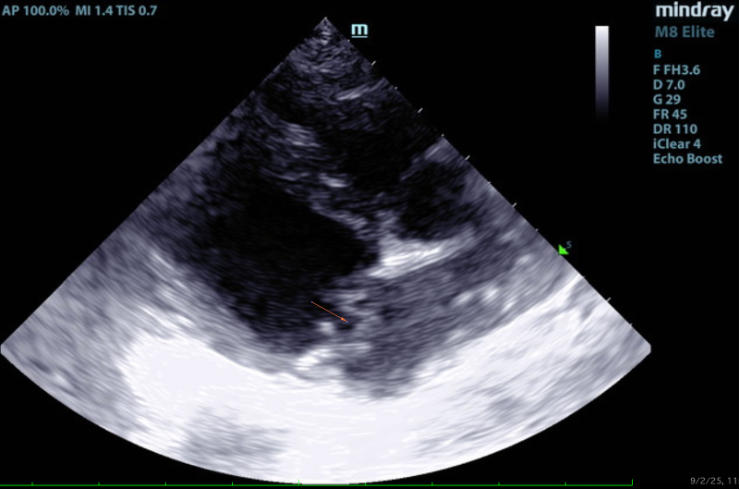

There is moderate left atrial enlargement. There is mild left ventricular dilation. Left ventricular systolic function is adequate. There is normal systolic flow velocity across the aortic valve; no insufficiency. The aortic valve appears normal. Mild right atrial/ventricular enlargement. The tricuspid valve is mildly thickened with moderate tricuspid regurgitation. The tricuspid regurgitant velocity is consistent with moderate to severe pulmonary hypertension (PH). The pulmonary artery is prominent. Normal aortic and pulmonic outflow velocities. No aortic insufficiency (AI) or pulmonary insufficiency (PI). No pericardial/pleural effusion or cardiac masses are seen.

In this patient there is moderate left atrial enlargement, mild left ventricular enlargement, and mild right atrial and ventricular enlargement.

Chronic degenerative valve disease is causing moderate mitral and tricuspid regurgitation.